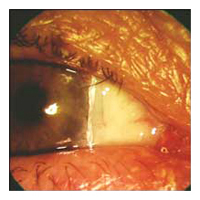

Before Pterygium Removal  After

Pterygium Removal

Pterygium (pronounced "tur-RIDGE-ium")

is a pinkish-yellow, triangular-shaped benign tissue growth starting

from the nasal area of your eye and grows toward the cornea. As

a pterygium grows, it can be varied in its appearance from small

and pink to large and angry red with symptoms of dry eye. Eventually,

it may cause visual disturbances by disrupting the normally smooth

surface of the cornea. In severe cases, a pterygium can block a

patient's vision altogether.